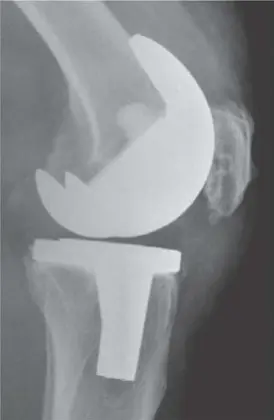

مكونات مفصل الركبة الصناعي

عندما يتلف مفصل الركبة الطبيعي بشكل لا يمكن إصلاحه (عادة بسبب التهاب المفاصل الشديد)، يتم استبداله بمفصل صناعي يتكون من عدة أجزاء:

- المكون الفخذي (Femoral Component): غطاء معدني (عادة سبيكة من الكروم والكوبالت) يلتف حول نهاية عظم الفخذ.

- المكون الظنبوبي (Tibial Component): يتكون من جزأين: صفيحة معدنية مسطحة (عادة سبيكة من التيتانيوم) تُثبت على قمة عظم الساق، وقطعة بلاستيكية (بوليثيلين) تُثبت فوقها. هذه القطعة البلاستيكية تعمل كغضروف صناعي، مما يتيح الحركة السلسة.

- المكون الرضفي (Patellar Component): قطعة بلاستيكية صغيرة تُثبت على السطح الخلفي للرضفة في بعض الحالات.

تُثبت هذه المكونات عادةً باستخدام إسمنت عظمي خاص يربطها بالعظام. يسمح هذا التصميم للمفصل الصناعي بمحاكاة حركة المفصل الطبيعي، مما يقلل الألم ويحسن الوظيفة.

- الأشعة السينية (X-ray): تُظهر المفصل الصناعي وتساعد في تقييم استقراره، وتحديد وجود أي تراخي أو تآكل في العظام حول المفصل، والذي قد يكون علامة على العدوى المزمنة.